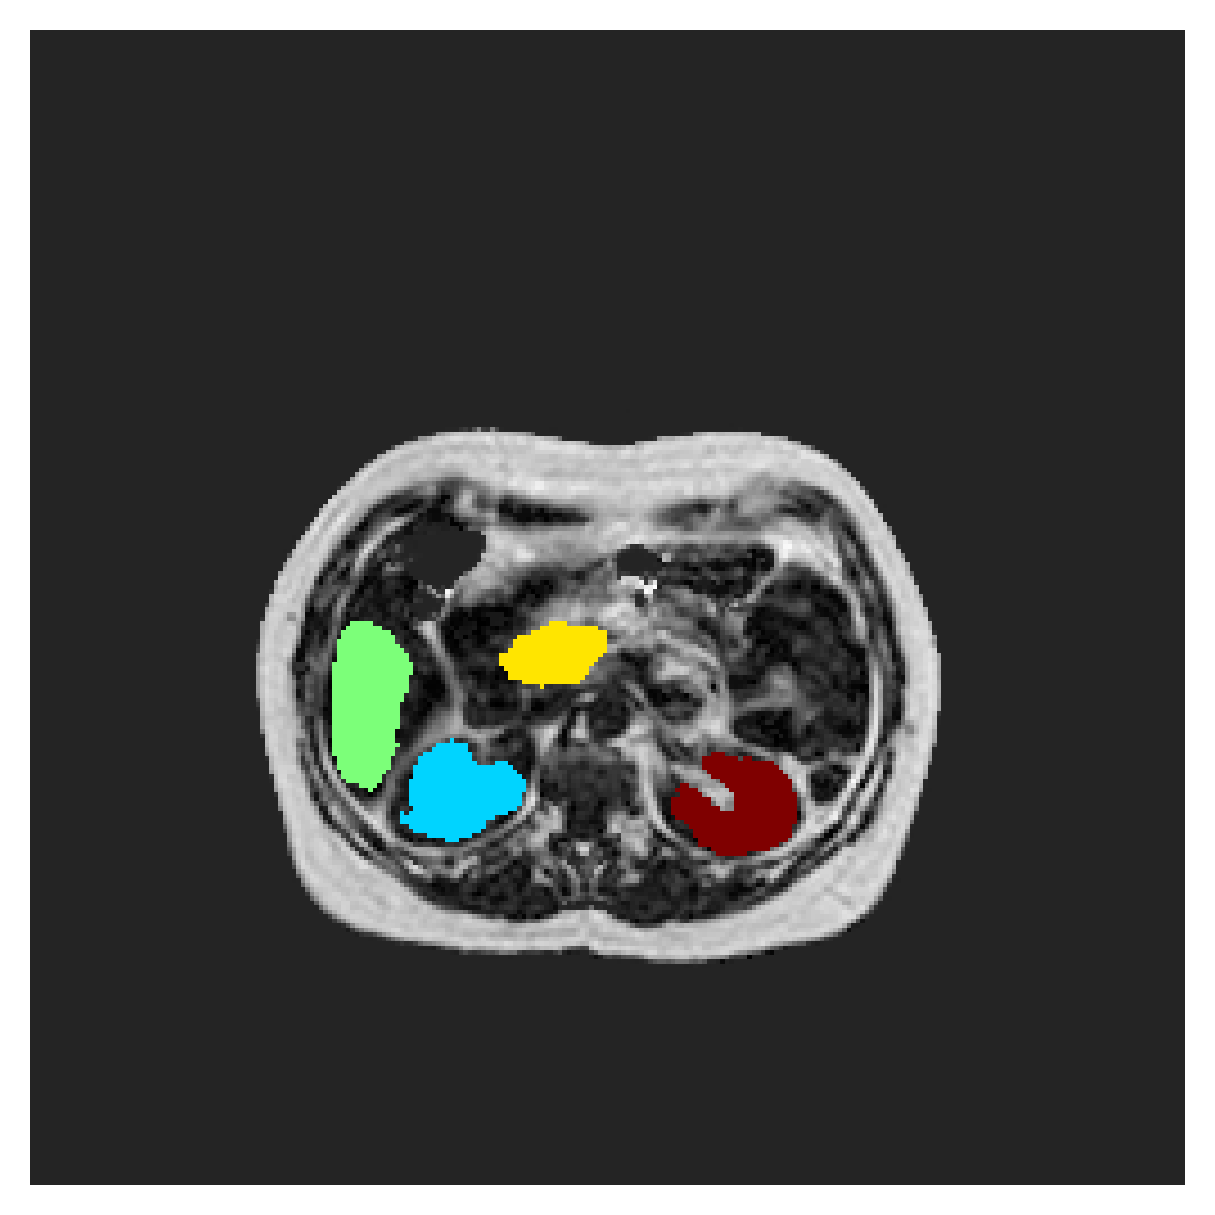

POEM

The Prospective investigation of Obesity, ENergy production and Metabolism (POEM) is a local (not currently publicly available; PI: L. Lind, see [22] for details) cohort of whole-body fat/water separated MR images. Full annotations of the liver, kidneys, bladder, pancreas and spleen are available for 50 subjects, providing a challenging segmentation dataset with heavily imbalanced classes of varying shapes. The resolution of the data is anisotropic, with reconstructed voxel size of in left-right, anterior-posterior and foot-head directions, respectively. For additional technical details regarding the acquisition and specifications of the images see [22].

The images contain two channels, one for water and one for fat content. For training, we normalize the volumes (per channel) and use 2D slices in the coronal plane, sized . The weak annotations are created synthetically, following the same procedure as described for the ACDC dataset.

In Table 3, the average DSC and HD95 results are shown (both using 2D and 3D distance maps) for the task of abdominal organ segmentation in POEM data (for boxplots see figures 8 and 9). We see that training with and (with distances calculated on 2D slices) performs comparably, while using and produces lower scores in both DSC and HD95 metric. On this dataset, the CRF-loss is able to compete with the boundary loss-based training strategies, even outperforming them on most classes. Most notably, all models trained with boundary loss appear to have a hard time segmenting the liver. We hypothesize this may be due to extremely severe class imbalance, as the liver covers a very large area compared to the rest of the classes. It is thus also more strongly affected by undersegmentations.

5.2.1 Qualitative comparison

In Figure 11 and 12 we show the same random slices in cases of calculating the boundary loss on 2D- and 3D-based distances, respectively. Comparing the two figures again indicates that the intensity-aware distances offer most improvement when calculated in 3D over 2D. The exception here is the MBD, which seems to even slightly degrade for most classes.